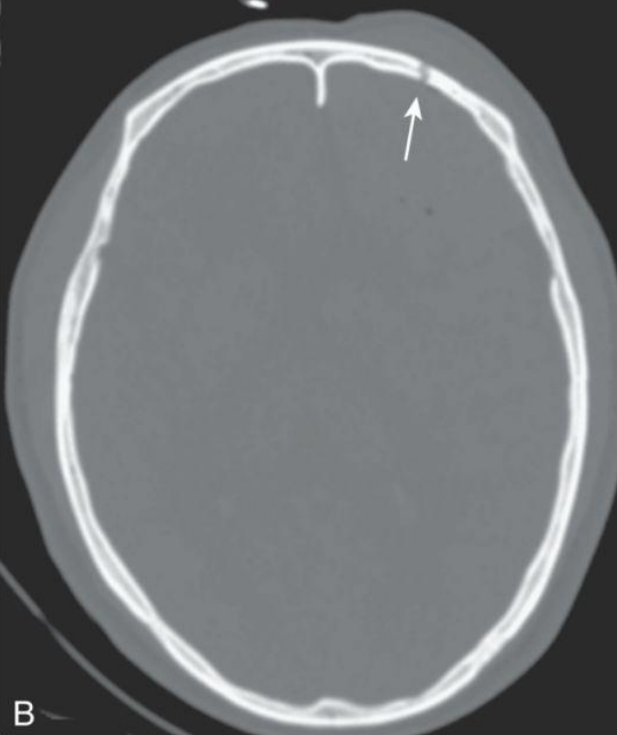

Fractura lineal: hallazgos

A

Línea radiolucente fina; temporal/parietal + frec

7

Q

Fractura deprimida: imagen clave

Zona común:

Hundimiento del hueso; mejor en TC 3D.

Frontoparietal